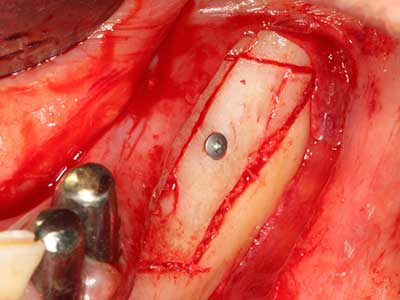

La piezochirurgia presenta altri vantaggi per quanto riguarda la raccolta di blocchi ossei. Oltre all'elevata precisione dell'osteotomia appena descritta, l'utilizzo di puntine per sega molto sottili permette di minimizzare in maniera significativa la perdita di materiale. È molto probabile che si verifichi una maggiore perdita di materiale durante la raccolta utilizzando puntine di strumenti più spessi, in particolare delle frese Lindemann (Lakshmiganthan, Gokulanathan et al. 2012). La separazione basale, necessaria in particolare per i trapianti di blocchi nella zona retromolare, viene semplificata grazie a seghe specificatamente progettate di forma rettangolare; di conseguenza la piezochirurgia è considerata una procedura precisa, semplice e sicura per la raccolta di blocchi di osso nella zona retromolare (Happe 2007) (figg. 1-12).